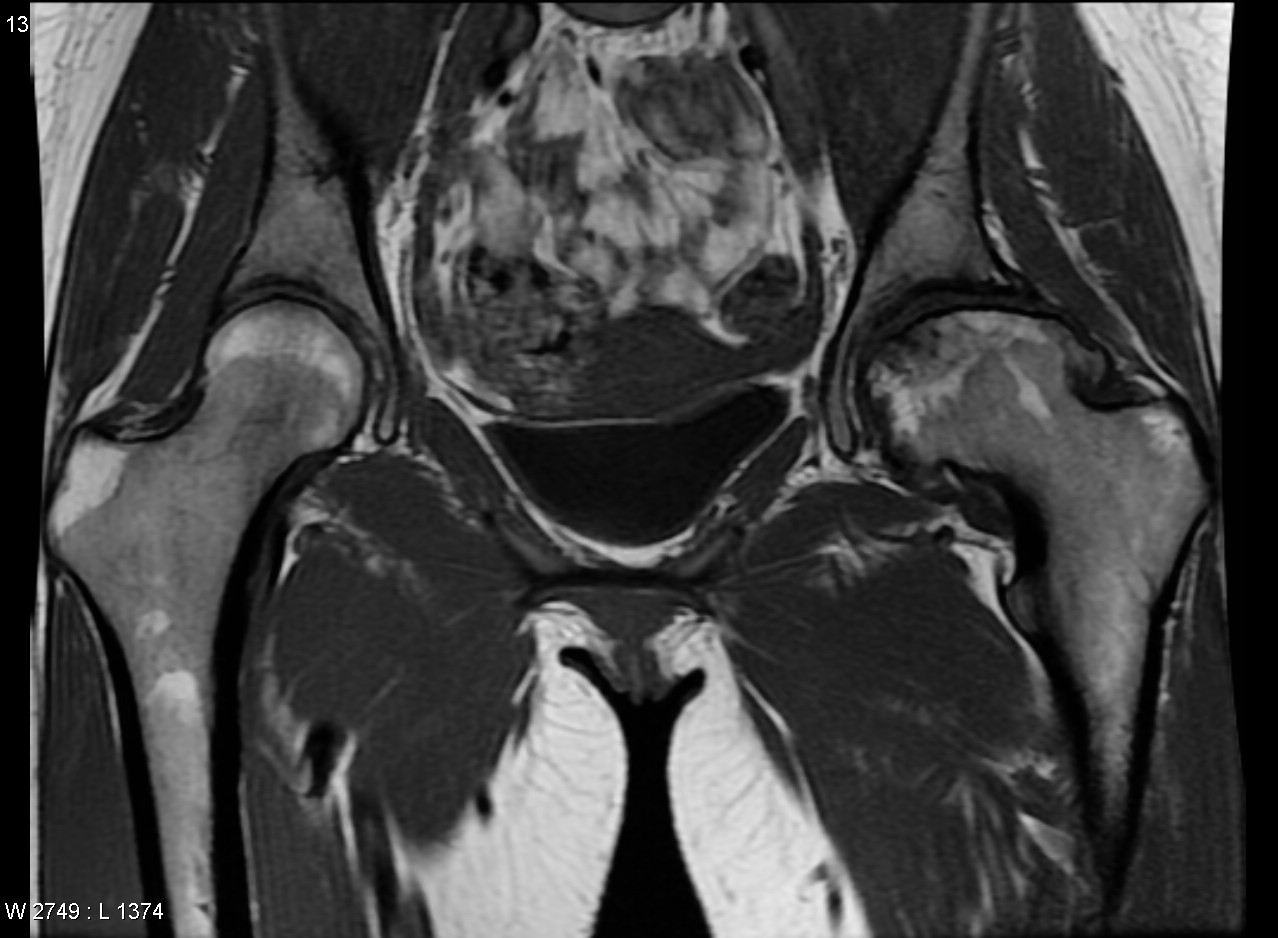

Некроз тазобедренного сустава: Фотографии и особенности лечения